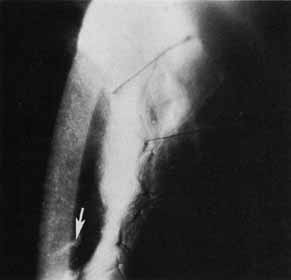

Multiple topical anesthetic drops and antibiotic drops are applied, and the patient is instructed to hold the eye very still during the adjustment to avoid the risk of breaking the single running suture. Comfortable positioning at the slit lamp is essential. Blunt-tipped microtying forceps are used to break the epithelium and anterior stromal adhesions in the graft–host interface for 360 degrees. After the relatively tight (steep) meridians are determined, the forceps are used to gently pull individual loops, sequentially moving the suture away from the flat (loose) meridian toward the steep meridian, thereby redistributing suture tension (Fig. 11). A drop of artificial tears is placed on the cornea, and a handheld keratoscope is used to reassess the corneal curvature. The adjustment process is repeated until circular mires are noted on keratoscopy. Antibiotic drops are again placed on the eye; a patch is optional but not usually necessary. We use a broad-spectrum topical antibiotic drop, such as a fluoroquinolone, in addition to the usual topical corticosteroid drops four times daily for 1 week after suture adjustment. The patient returns in 1 to 3 weeks when the process can be repeated if greater than 2 to 3 diopters (D) of corneal astigmatism persist. Spectacle correction can be provided approximately 4 weeks after suture adjustment as the cornea appears to be relatively stable at that time. The remainder of the postoperative care is per regular routine.

Fig. 11 Schematic example of the single continuous suture. Ten diopters (50.00 D-40.00 D) of postkeratoplasty astigmatism are present at axis 90 degrees. By using straight tying forceps at the slit lamp, loose suture from the horizontal axis is gently pulled into the vertical axis where suture tension is high. Arrowhead represents the direction of individual suture pull to reduce suture tension in tight meridian. Bowed arrow represents general direction of suture adjustment. (From Van Meter WS, Gussler JR, Soloman KD, Wood TO: Postkeratoplasty astigmatism control. Ophthalmology 98:179, 1991, with permission)